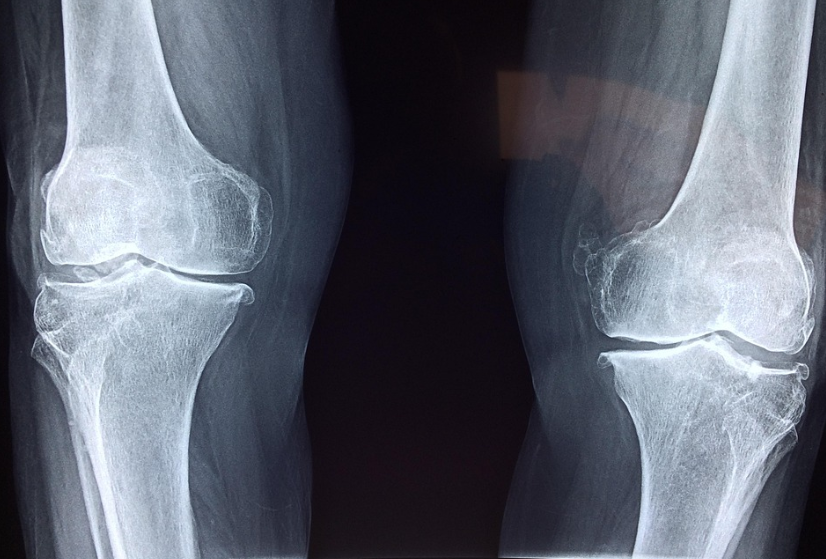

🔍 "나이가 들수록 연골이 닳고 관절염 위험이 증가한다!"

✔ 연골이 점점 얇아지고 관절 마모 진행

✔ 퇴행성 관절염, 류마티스 관절염 발생 가능성 증가

✔ 무릎, 어깨, 손목 관절 통증이 일상생활에 영향을 미침